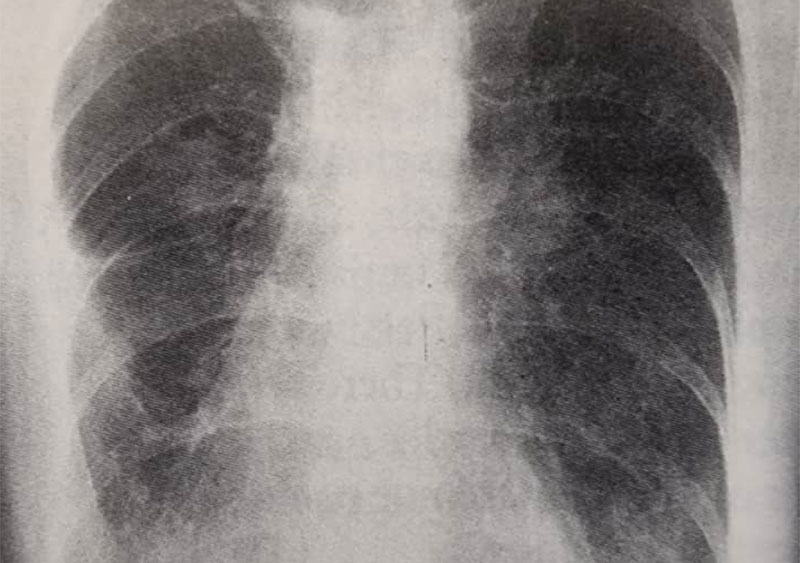

این فرد بیماری مدیاستینال داشت (تصویر55d) و با چهار دوره شیمی درمانی و بدنبال آن پرتودرمانی تحت درمان قرار گرفت. اگرچه در رادیوگرافی که 2سال بعد تهیه شد (تصویر55e) علایم بهبودی از بیماری هودجکین نشان داده شد اما شواهدی از افزایش سایه های دوطرفه در نواحی تحتانی دیده می شود و در بیمار پنمونیت ناشی از پرتودرمانی ایجاد شد که به درمان با استروئید پاسخ داد.